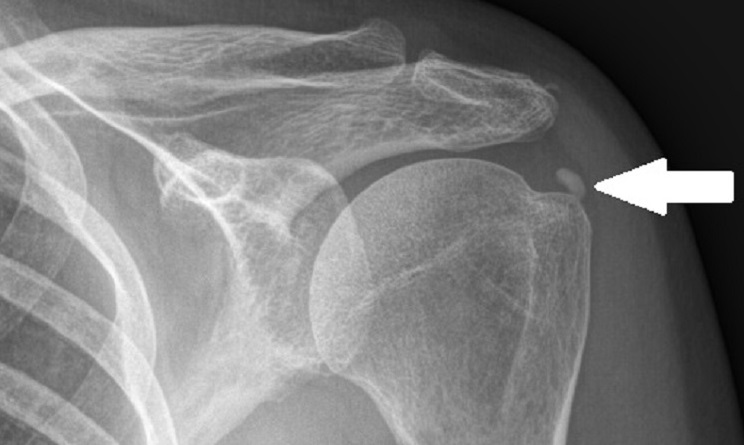

Calcificación de Manguito Rodador. Tendinitis Cálcica de Supraespinoso

Las calificaciones en el manguito rotador son hallazgos radiológicos relativamente frecuentes entre el 2 al 20% de los casos. La edad de aparición es en general de la tercera a la quita decana de la vida. Puede estar asociada a dolor y disfunción del hombro. El tendón más comúnmente afectado es el supraespinoso, en el hombro

Llamativamente no es la forma de estudiarlas ya que en el calcio en la resonancia se ve color negro al igual que el tendón y eso dificulta su hallazgo, de todas formas, una vez hecho el diagnostico se solicita una resonancia para descartar lesiones asociadas. La radiografía y la tomografía son estudios radiológicos muy útiles para hacer diagnóstico de su ubicación y tamaño en el hombro.